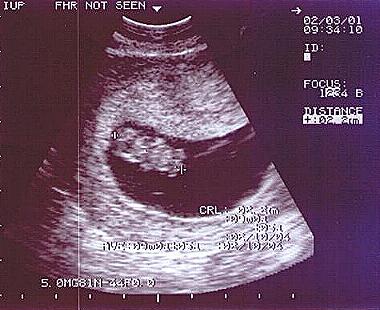

Tucked Beneath Mommy’s Heart..

I’m the size of a peanut and so very small…

And if you looked for me, you’d see nothing at all…

But Mommy and Daddy, know right where I am…

They touch me and call me, their own little lamb…

I’m tucked safe beneath, my mommy’s warm heart..

And this is the place my life journey will start…